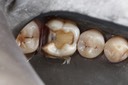

Mark Chun #14 caries removal